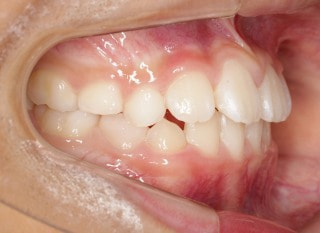

小児期第一段階

終了時